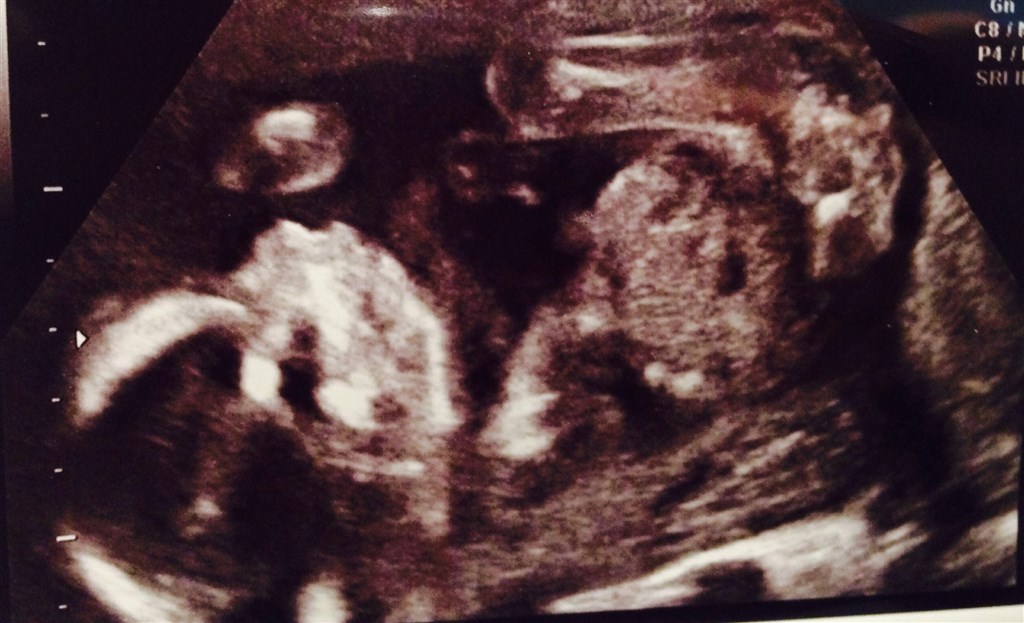

Var til scanning idag.

Så dejligt når man ser det hele bare er perfekt, som skal være��